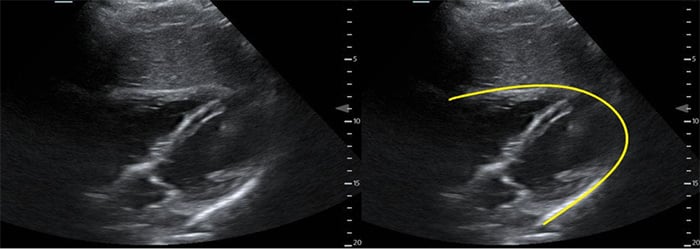

- With the transducer in the subxyphoid region, transducer in the transverse plane, evaluate the periaortic region for large lymph nodes. (Figure 1, #2)

- Identify the arch of the vertebral body in the far field then the aorta just to the patient’s left.

- Identify the “seagull sign” of the celiac trunk and slide the transducer inferiorly to the bifurcation of the common iliac arteries.

- Normally, lymph nodes will be difficult to visualize because they are small and normally hypoechoic with a hyperechoic central hilum. As they enlarge, the architecture is distorted, and they develop a homogeneous echotexture. Attempt to image lymph nodes in 2 planes and measure the diameter.

Figure 3. Proximal aorta (A) with celiac trunk "seagull sign" (*) adjacent to the IVC and vertebral body (V)